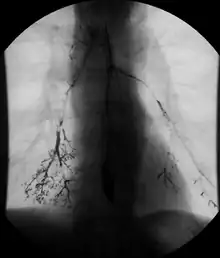

An upper gastrointestinal series, also called a barium meal, is a series of radiographs used to examine the gastrointestinal tract for abnormalities. A contrast medium, usually a radiocontrast agent such as barium sulfate mixed with water, is ingested or instilled into the gastrointestinal tract, and X-rays are used to create radiographs of the regions of interest. The barium enhances the visibility of the relevant parts of the gastrointestinal tract by coating the inside wall of the tract and appearing white on the film. This in combination with other plain radiographs allows for the imaging of parts of the upper gastrointestinal tract such as the pharynx, larynx, esophagus, stomach, and small intestine such that the inside wall lining, size, shape, contour, and patency are visible to the examiner. With fluoroscopy, it is also possible to visualize the functional movement of examined organs such as swallowing, peristalsis, or sphincter closure. Depending on the organs to be examined, barium radiographs can be classified into "barium swallow", "barium meal", "barium follow-through", and "enteroclysis" ("small bowel enema"). To further enhance the quality of images, air or gas is sometimes introduced into the gastrointestinal tract in addition to barium, and this procedure is called double-contrast imaging. In this case the gas is referred to as the negative contrast medium. Traditionally the images produced with barium contrast are made with plain-film radiography, but computed tomography is also used in combination with barium contrast, in which case the procedure is called "CT enterography".[1]

Various types of barium X-ray examinations are used to examine different parts of the gastrointestinal tract. These include barium swallow, barium meal, barium follow-through, and barium enema.[2] The barium swallow, barium meal, and barium follow-through are together also called an upper gastrointestinal series (or study), whereas the barium enema is called a lower gastrointestinal series (or study).[3] In upper gastrointestinal series examinations, the barium sulfate is mixed with water and swallowed orally, whereas in the lower gastrointestinal series (barium enema), the barium contrast agent is administered as an enema through a small tube inserted into the rectum.[2]

Barium swallow

Little or no preparations are required for the study of the larynx, pharynx, and esophagus when studied alone.[11] A thick barium mixture is swallowed in supine position and fluoroscopic images of the swallowing process are made. Then several swallows of a thin barium mixture are taken and the passage is recorded by fluoroscopy and standard radiographs. The procedure is repeated several times with the examination table tilted at various angles. A total of 350-450 mL of barium is swallowed during the process.[12][13] Normally, 90% of ingested fluid should have passed into the stomach after 15 seconds.[14]